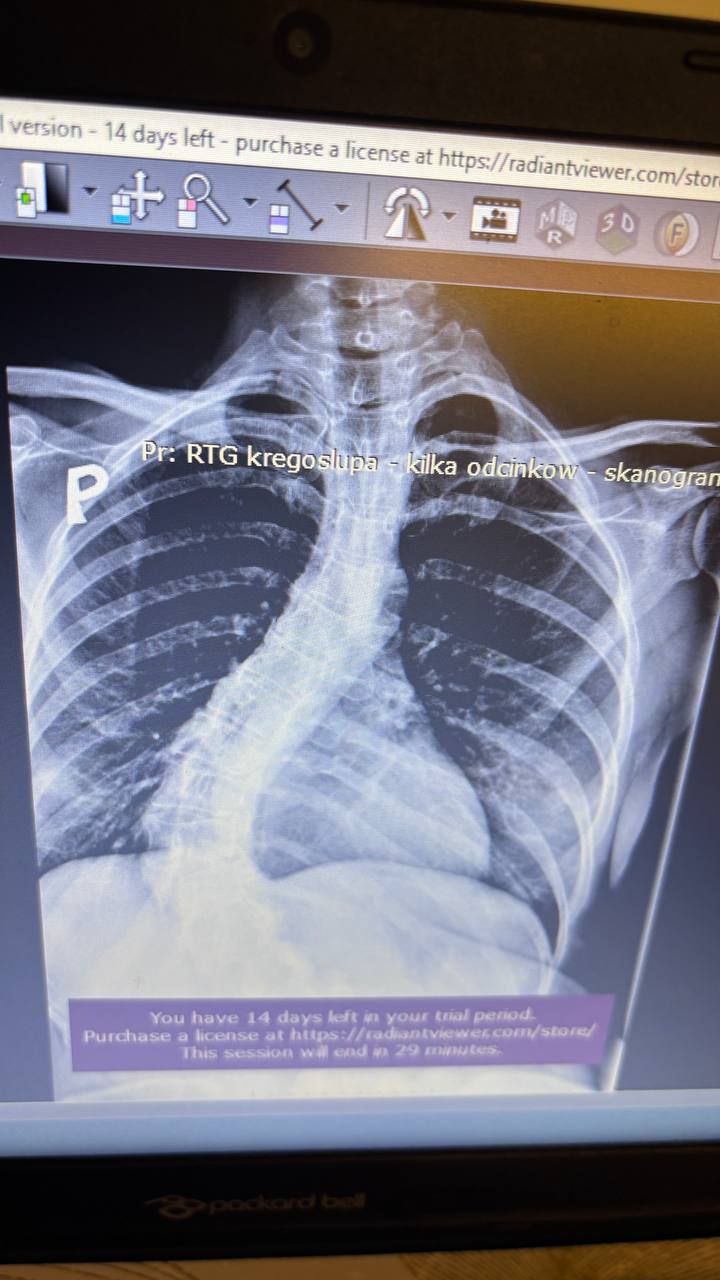

Діагноз: Ідіопатична сколіотична деформація хребта в дорослому віці. Правобічний реберний горб.

Сколіотична деформація хребта — це не лише викривлення спини.

У дорослому віці тяжкий сколіоз часто продовжує прогресувати на 1–3° щороку, поступово руйнуючи хребет.